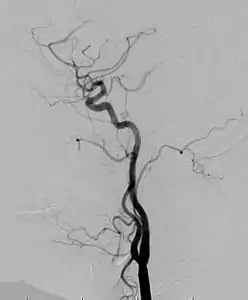

Angiogram: an angiogram can also be ordered to get a detailed look at the blood vessels in the affected or overgrown limb. In this test a physician injects a dye into the blood vessels that will help see how the blood vessels are malformed.[23]

Angiogram